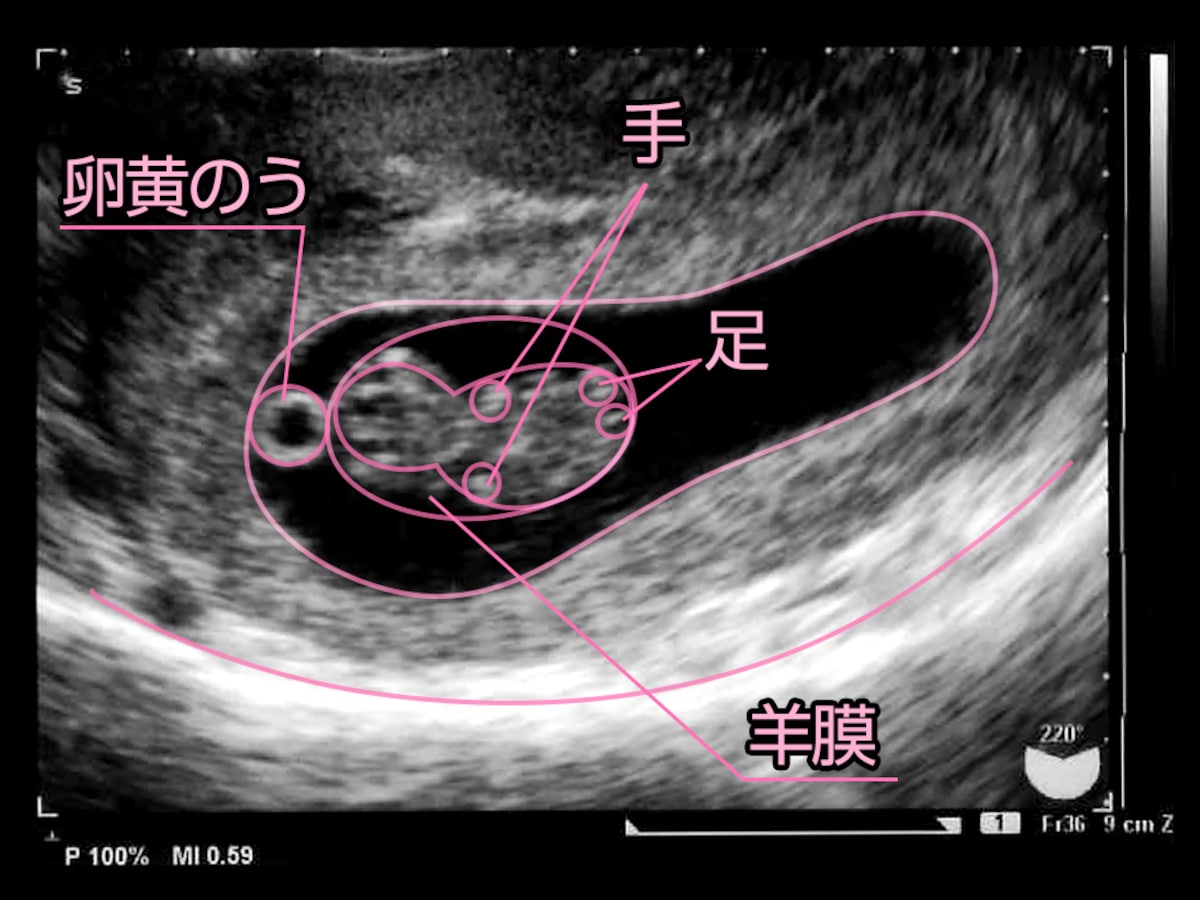

5 産科一般超音波検査 初期編 正常所見4 7週 日本産婦人科医会

5 産科一般超音波検査 初期編 正常所見4 7週 日本産婦人科医会

超音波写真館 妊娠初期4 7週 超音波教室 ママニティ大百科